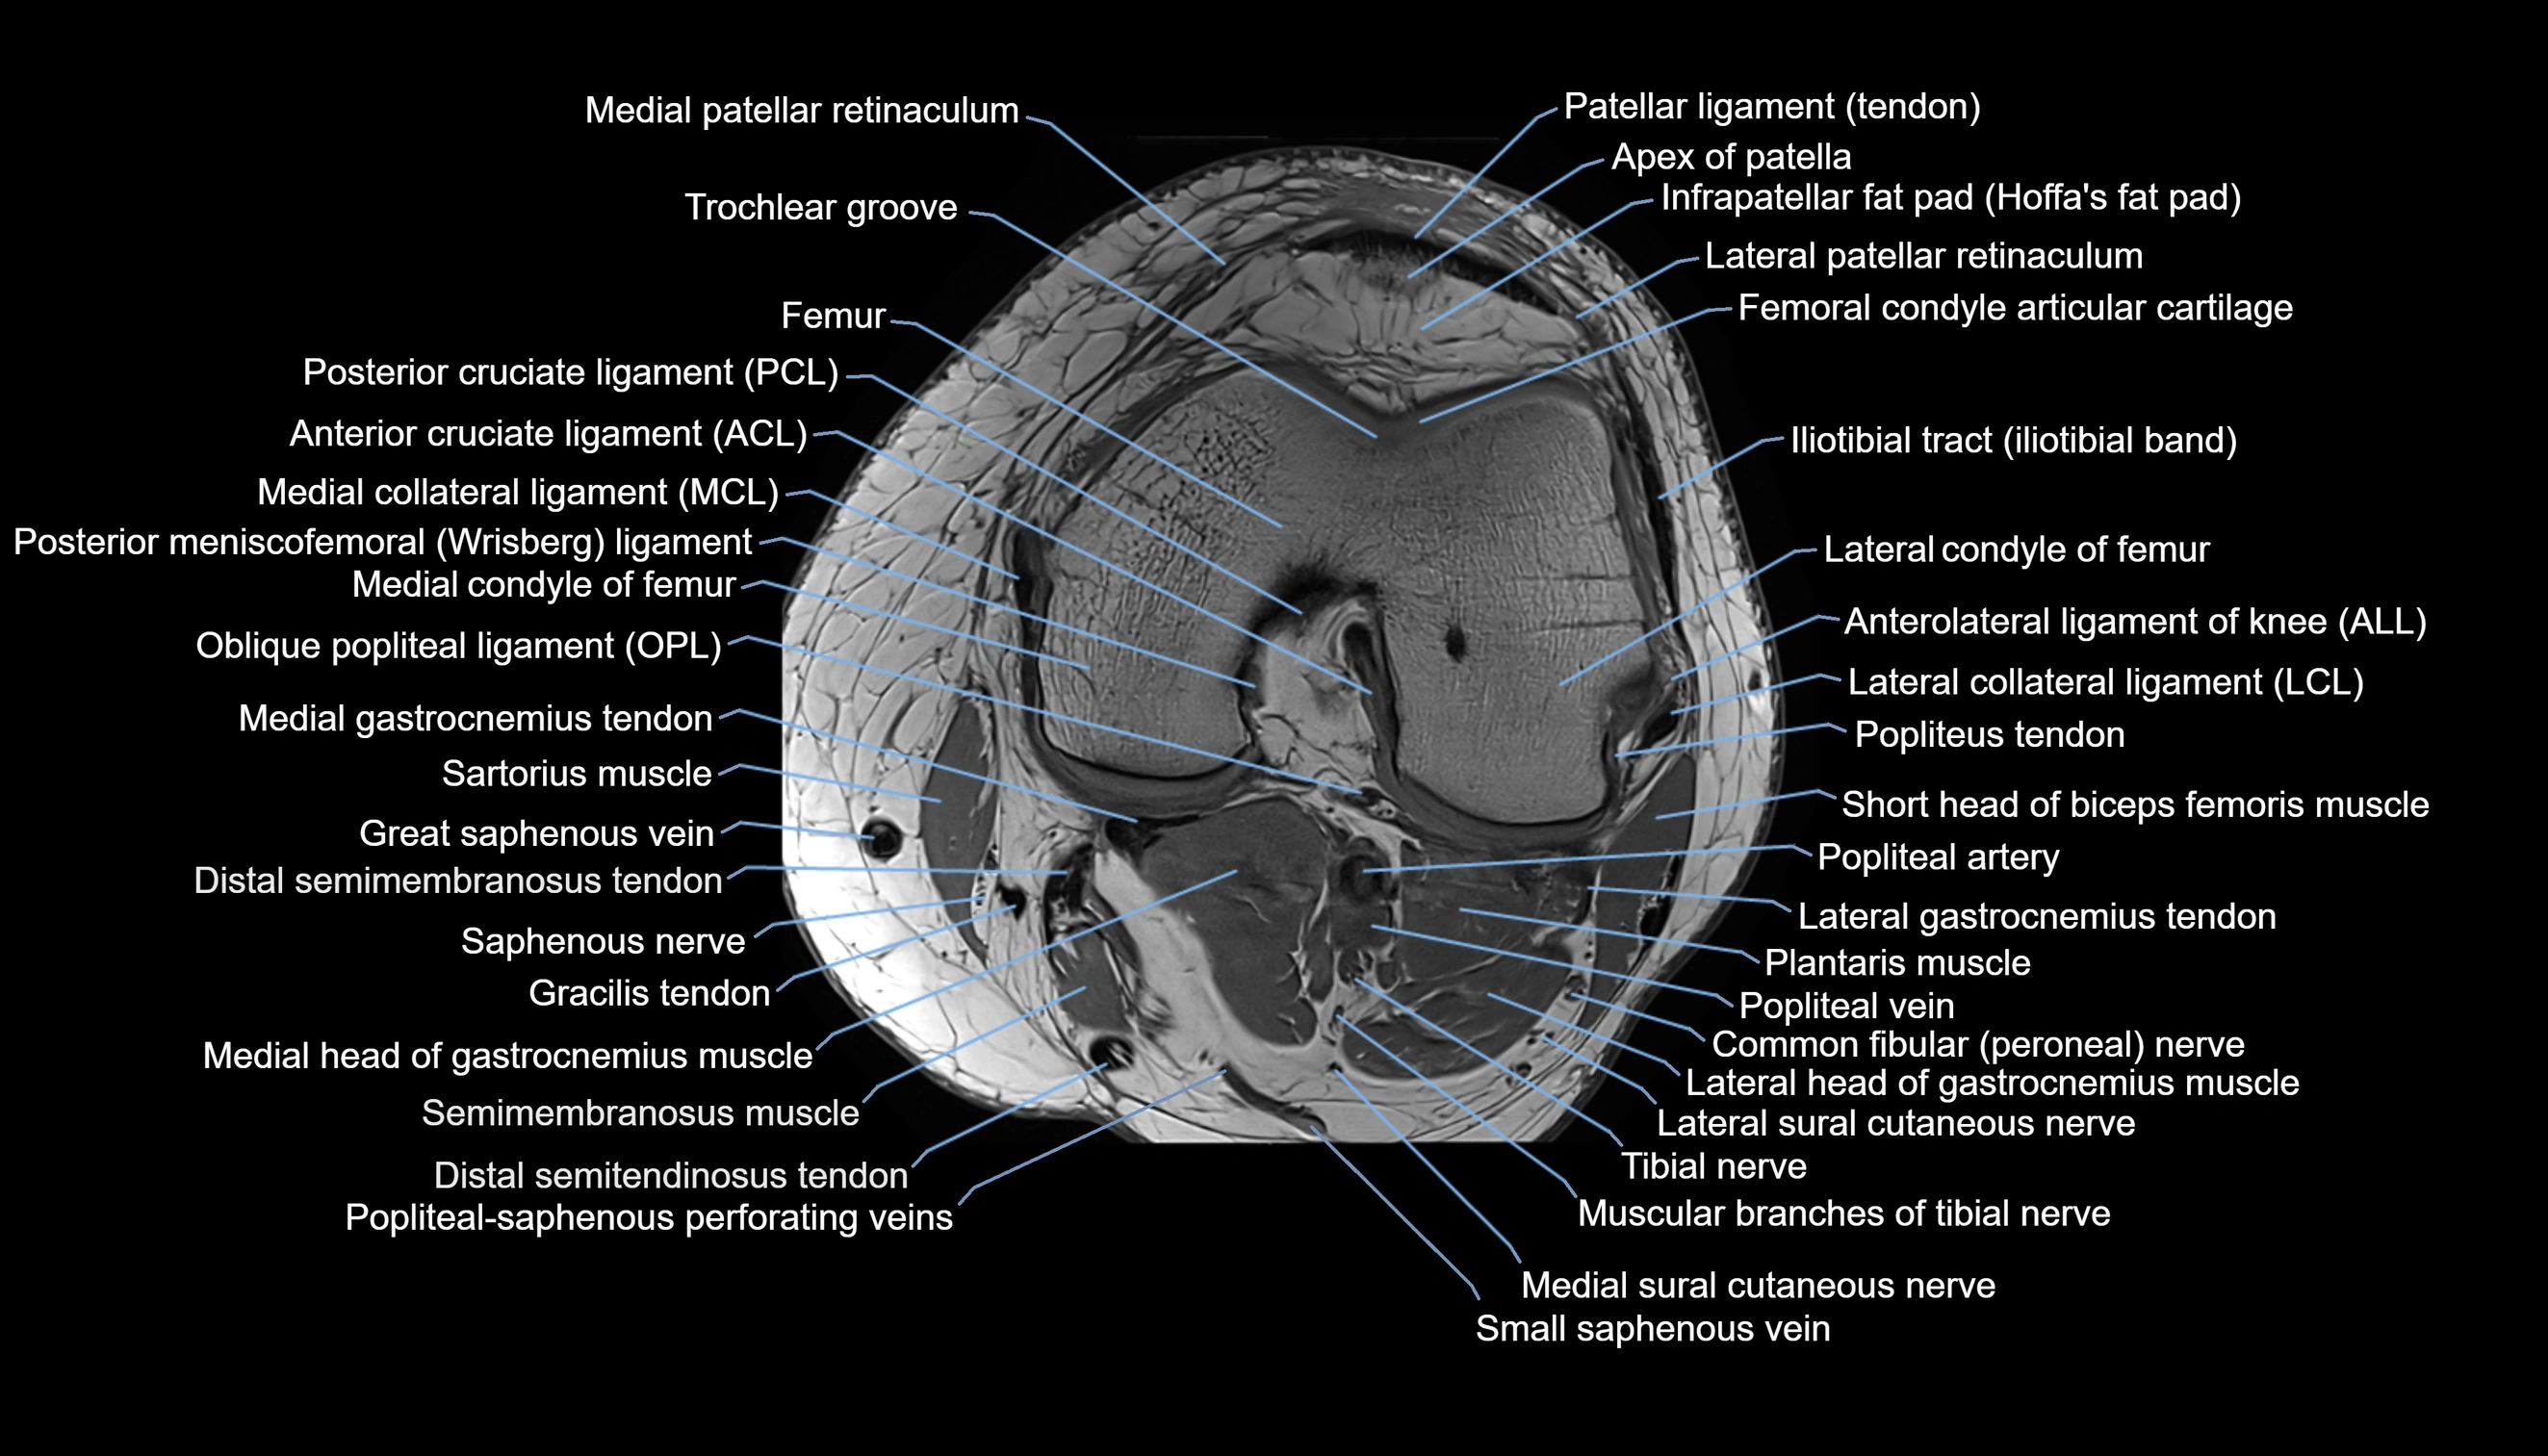

- Anterior cruciate ligament

- Posterior cruciate ligament

- Medial collateral ligament

- Lateral collateral ligament

- Oblique popliteal ligament

- Anterolateral ligament of knee

- Lateral patellofemoral ligament

- Lateral patellar retinaculum

- Femoral condyle articular cartilage

- Infrapatellar fat pad

- Patellar tendon (patellar ligament)

- Popliteus tendon

- Popliteal artery

- Popliteal vein

- Tibial nerve

- Lateral sural cutaneous nerve

- Medial sural cutaneous nerve

- Small saphenous vein

- Popliteal–Saphenous perforating veins